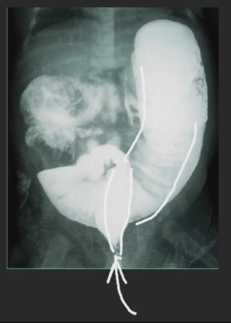

Diagnóstico de aganglionose intestinal congênita

1- enema opaco (contraste pelo reto): cone de transição